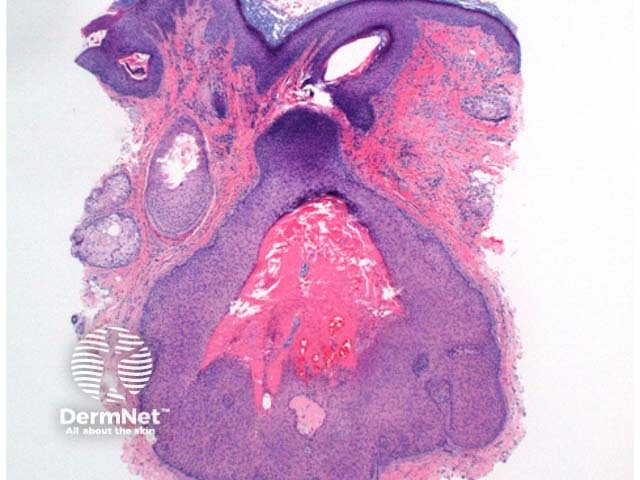

In pilar sheath acanthoma, there is a lobular proliferation of benign squamous epithelium in the dermis (figure 1, 2). These lobules surround small cystic spaces. The lining cells may have a granular layer similar to an epidermoid cyst (figure 3) or have an attenuated granular layer similar to a trichilemmal cyst (figure 4).

Figure 1